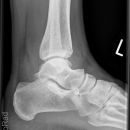

Totale Talusluxation